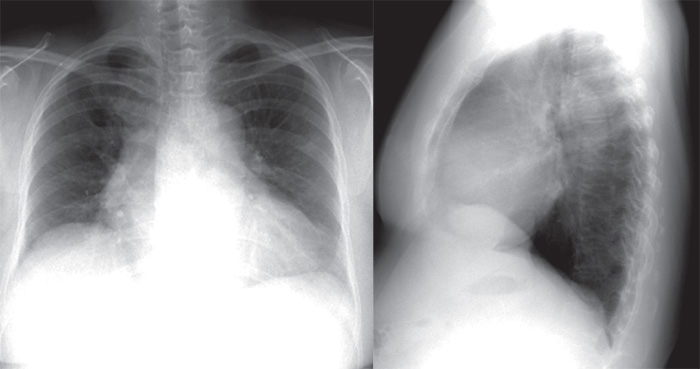

QUESTION NO.47